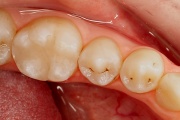

Hambakaaries

Lutipudelikaariese kahjustused

Lutipudelikaaries